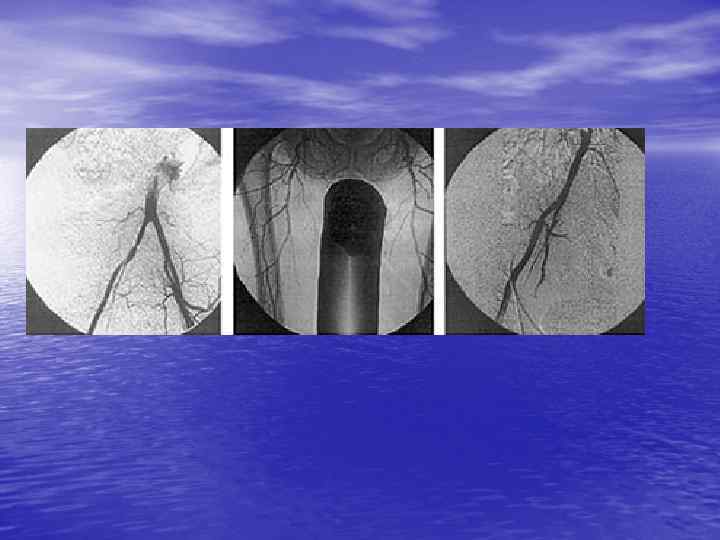

На ангиограмме